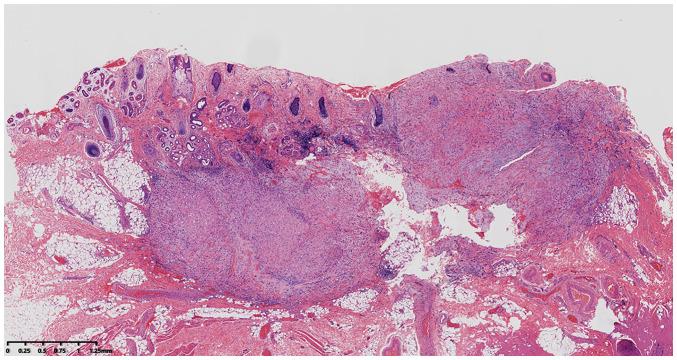

Eyelid epithelioid hemangioendothelioma (EHE) is uncommon. The present study reports the clinical, histopathological and immunohistochemical characteristics of a 10-year-old girl with EHE and reviews the related literature. The patient was admitted with a painless red mass on the left eyelid, which had been present for 6 months. Under the microscope, tumor cells from the surgical specimen were composed of epithelioid cells (70%) and spindle cells (30%). The cytoplasm was eosinophilic, and some areas of the cytoplasm showed signet ring-like or vacuolization changes. The presence of red blood cells could be seen in the luminal part of the primary blood vessel. Immunohistochemical results showed that the tumor cells were positive for CD34 and CD31, and the Ki-67 proliferation index was 3%. As the first resection margin was positive, recurrence occurred 3 months after surgery, Therefore, patients with such tumors should undergo full resections to ensure a negative margin to prevent recurrence.

眼睑上皮样血管内皮瘤(EHE)并不常见。本研究报告了一名患有EHE的10岁女孩的临床、组织病理学和免疫组化特征,并回顾了相关文献。该患者因左侧眼睑无痛性红色肿物入院,肿物已存在6个月。显微镜下,手术标本中的肿瘤细胞由上皮样细胞(70%)和梭形细胞(30%)组成。细胞质呈嗜酸性,部分细胞质区域呈印戒样或空泡样改变。在主要血管的管腔内可见红细胞。免疫组化结果显示肿瘤细胞CD34和CD31呈阳性,Ki-67增殖指数为3%。由于首次切除切缘阳性,术后3个月复发,因此,此类肿瘤患者应进行完整切除以确保切缘阴性,防止复发。